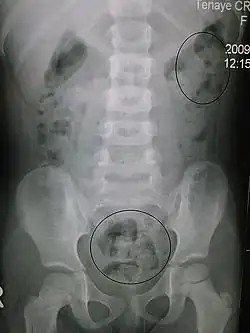

This image shows constipation in a young child as seen on X-ray.

In order to correctly manage neurogenic bowel dysfunction it is important to accurately diagnose it. This can be done by a variety of methods, the most commonly used would be taking a clinical history and carrying out physical examinations which may include: abdominal, neurological and rectal examinations.[26] Patients may use the Bristol Stool Chart to help them describe and characterise the morphological features of their stool, this is useful as it gives an indication of the transit time.[27] An objective method used to evaluate the motility of the colon and help with diagnosis is the colon transit time.[28] Another helpful test to diagnose this condition may be an abdominal X-ray as this can show the distribution of feces and show any abnormalities with the colon, for example a megacolon.[16]